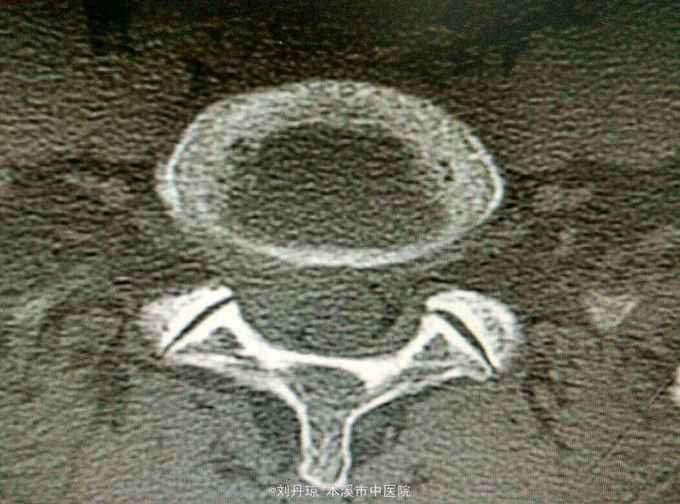

查体:L5—S1棘突旁压痛阳性。直腿抬高实验。左70度,右30度。加强试验左侧阴性,右侧阳性。腰椎功能障碍。CT:L5—S1椎间盘突出。